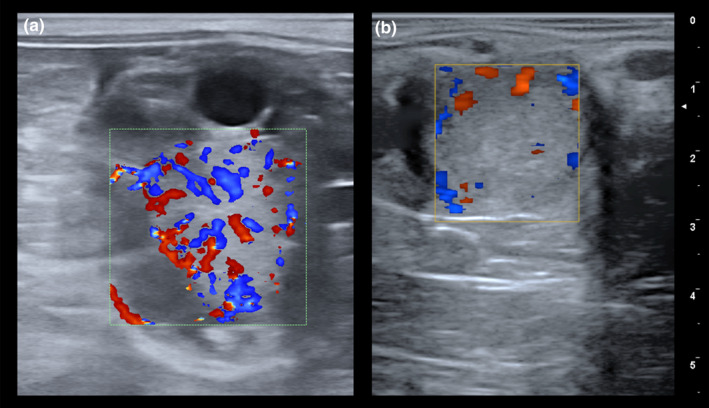

- 血供监测(彩超): 成熟黄体外围血管丰富,彩超显示环状彩色血流;若血流减少,预示黄体退化。

- 彩色血流不足:血供减少往往先于黄体萎缩,尤其在流产风险马匹中具重要价值。